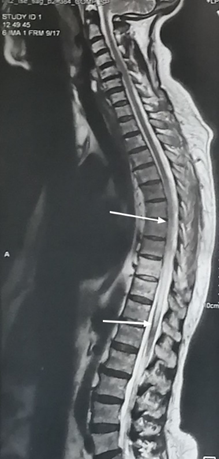

A whole spine MRI (Magnetic Resonance Imaging) revealed an intramedullary hyperintense signal on T2-weighted images extending longitudinally from D6 to D12 and transversally in axial planes. These findings indicated longitudinally extensive transverse myelitis (Figure 1 & 2). T1-weighted images following Gadolinium injection showed mild enhancement.

Figure 1 Sagittal T2-weighted whole spine MRI showing intramedullary hyperintensity extensive longitudinally from D6 to D12 (1a).